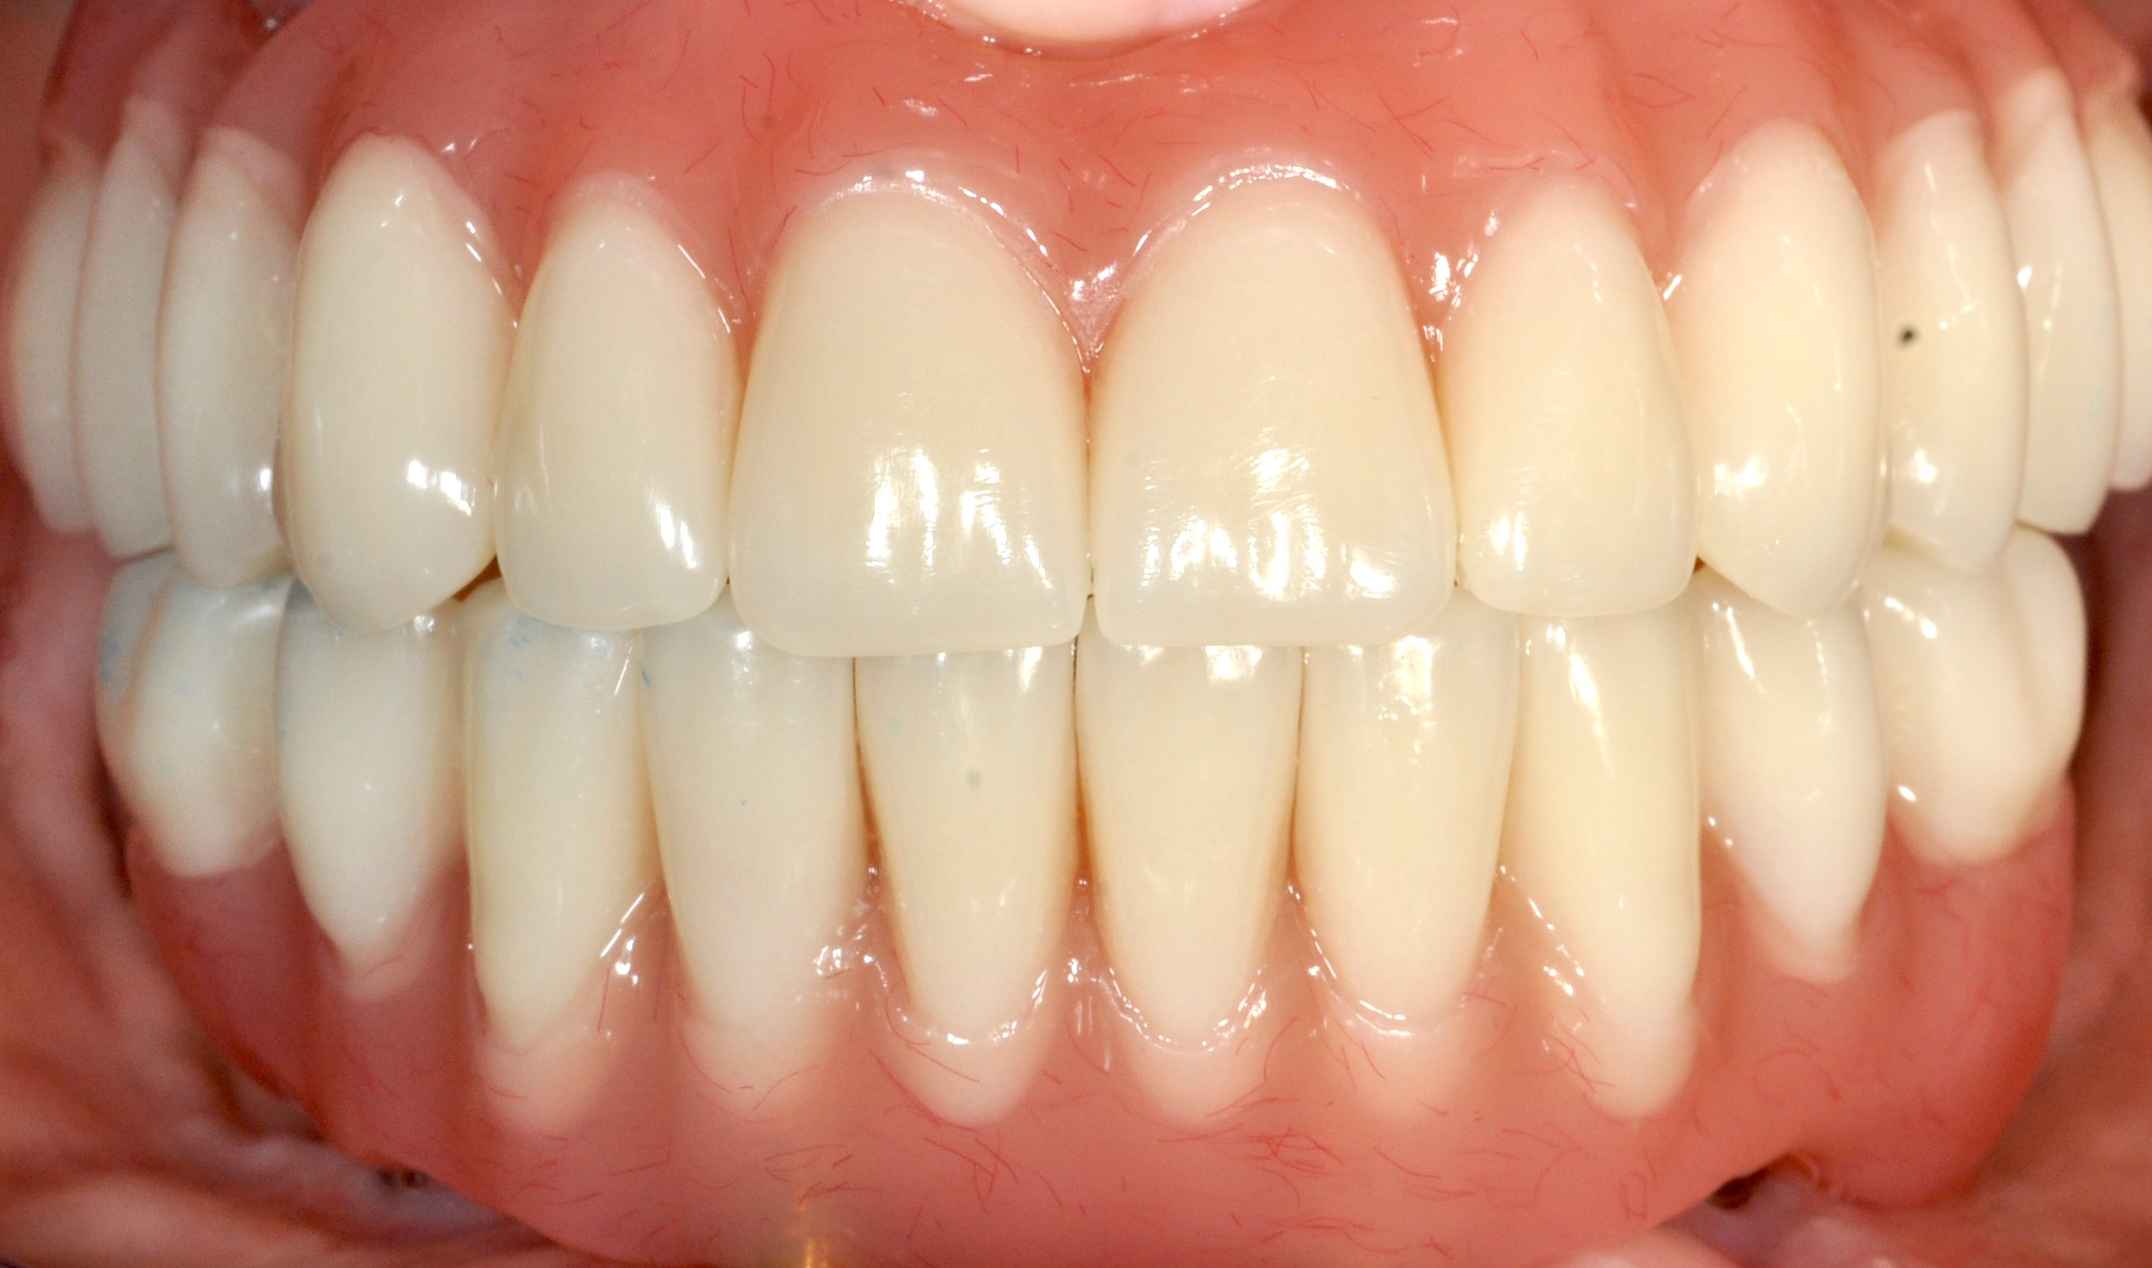

DOPO